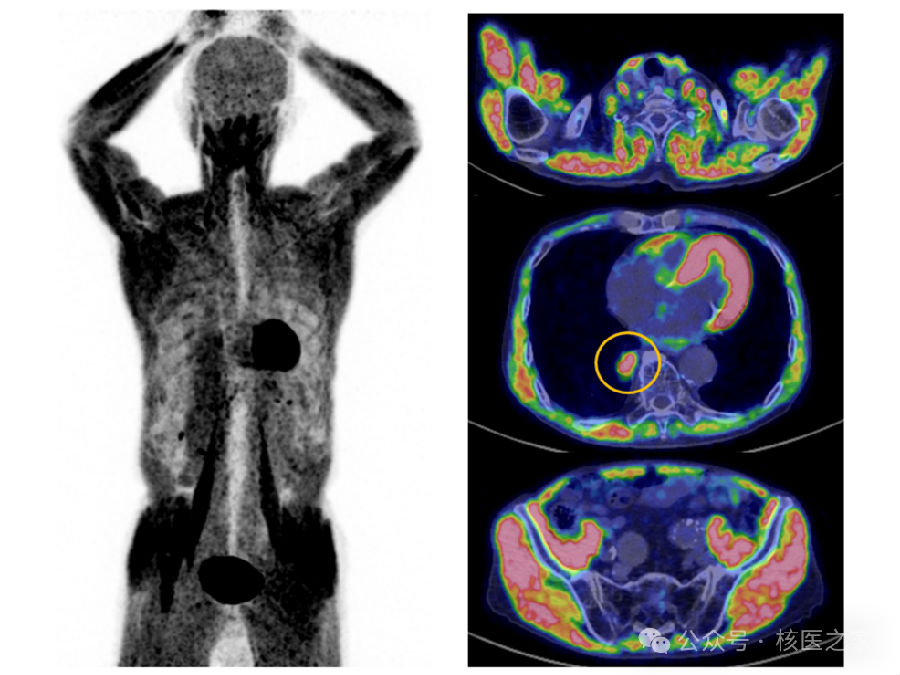

一位89岁男性,有肺癌手术及放疗史,PET/CT检查。检查前,患者同意空腹6小时。然而,在PET/CT检查前测得其血糖为153 mg/dL。影像结果显示全身骨骼肌摄取显著增强,最大标准摄取(SUVmax)达5.2(图1)。

图1.患者PET/CT图像。全身骨骼肌中可见高浓度的¹⁸F-氟脱氧葡糖(FDG)摄取。同时,在右下肺叶可见一处病灶亦有FDG积聚(黄色圆圈区域),考虑为肺癌复发病灶。

患者无糖尿病史,无肌肉相关症状,亦无包括肌炎在内的结缔组织病。同时,检查当日及前一日均未进行运动。胃内容物充盈明显(图2),提示其在检查前可能进食。尽管患者自述空腹,但考虑其高龄,可能遗忘了禁食要求。